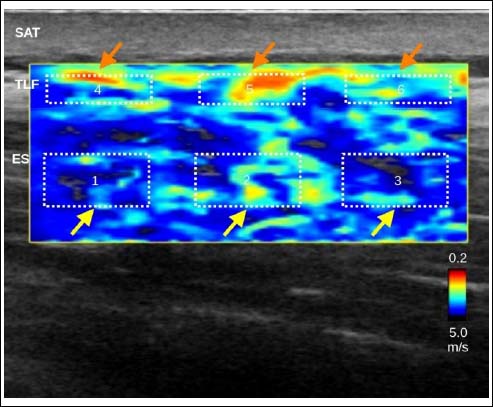

Figure 2.

Ultrasound elastography. Measurements were performed in equidistant rectangular areas within the thoracolumbar fascia (orange arrows) and the erector spinae muscle (yellow arrows). SAT, subcutaneous adipose tissue; ECT, extramuscular connective tissue; ES, erector spinae muscle.